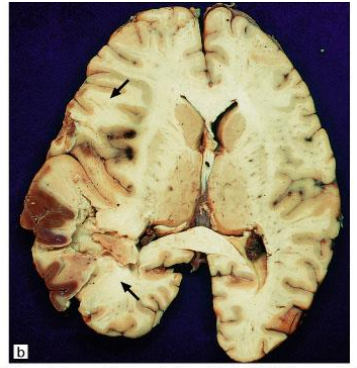

Hemorrhagic Infacts; can be venous (thrombus) or arterial (ischemia and reperfusion)

Venous Infarcts; most commonly seen parasagittally (in superior sagittal sinus distribution) or distribution of transverse sinus

Top: bilateral PCA infarcts from emboli can often become hemorrhagic (and can be multifocal)

Bottom: small clot/embolus (arrow) with surrounding hemorrhagic infarct